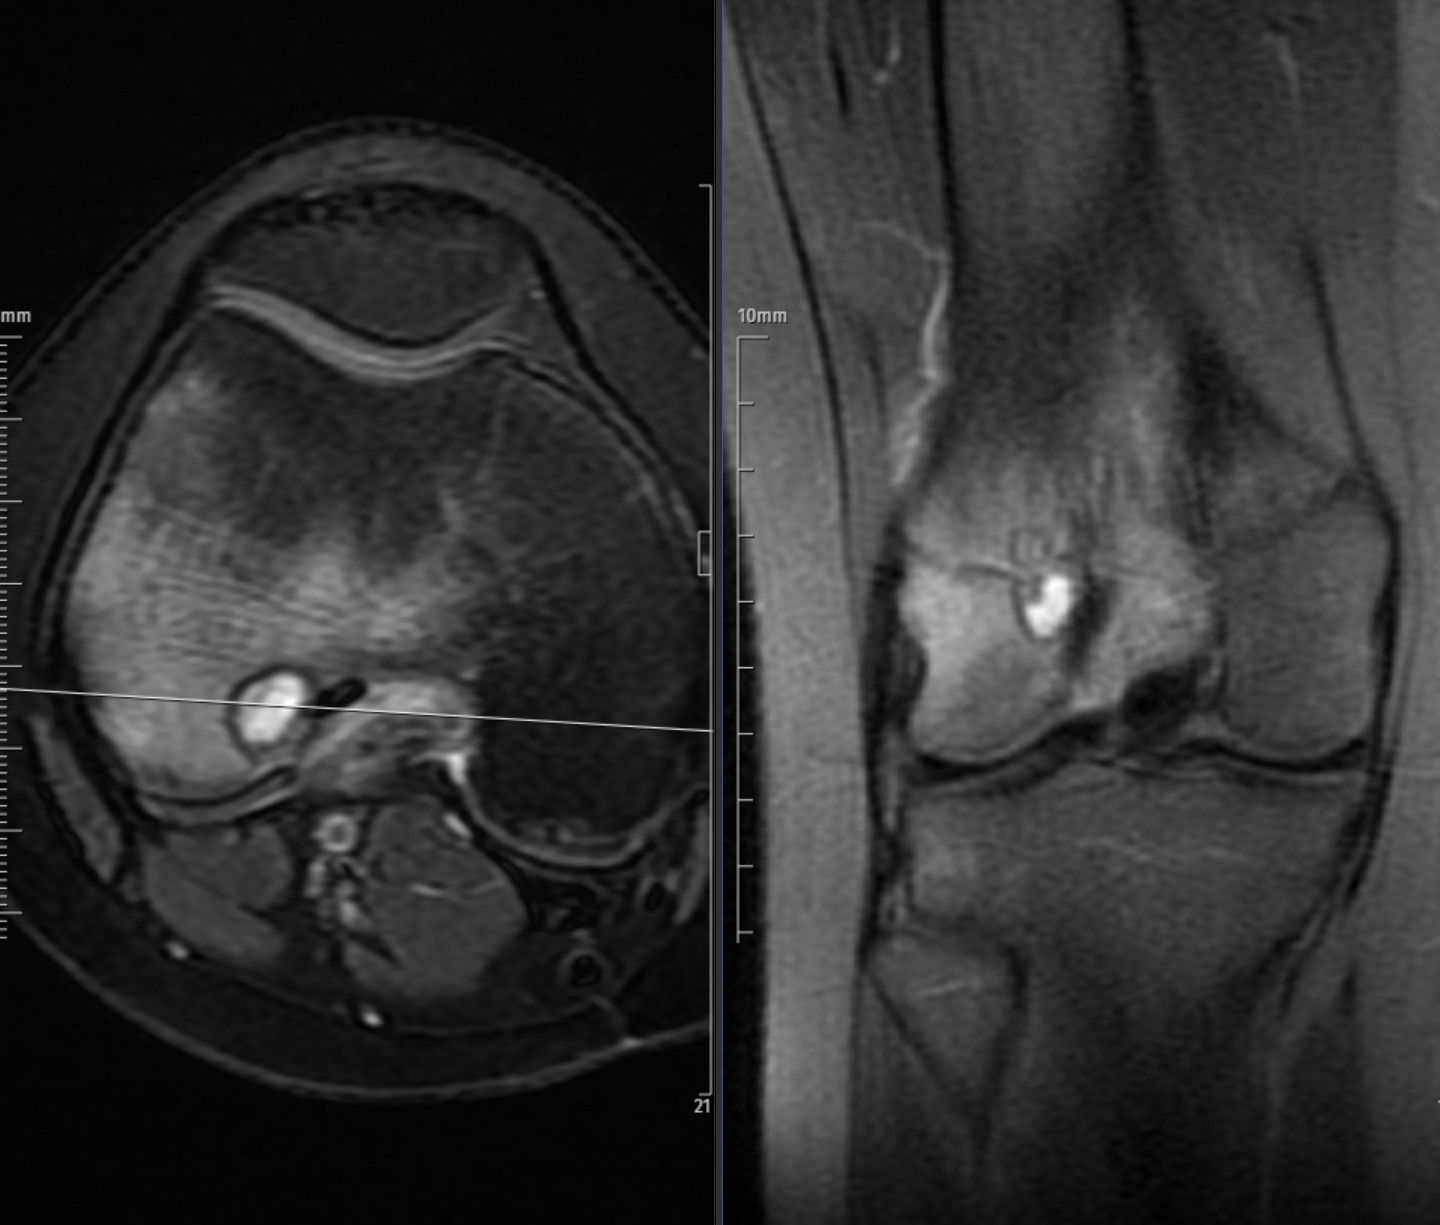

Chondroblastomas typically present as well-circumscribed, lobulated lytic lesions located in the epiphysis or apophysis of long bones, most often around the knee or proximal humerus. On radiographs, they demonstrate geographic bone destruction with a thin sclerotic margin and may contain subtle internal calcifications reflecting a chondroid matrix. CT better delineates these calcifications and cortical integrity.

On MRI, chondroblastomas usually appear heterogeneous, with intermediate signal intensity on T1-weighted and variable high signal on T2-weighted or fat-suppressed sequences, often surrounded by bone marrow and soft-tissue edema. A thin hypointense rim corresponding to reactive sclerosis is frequently seen. Post-contrast images show heterogeneous enhancement of the solid components and reactive tissues. Joint effusion or mild synovitis is common due to the subarticular location.

Overall, the imaging appearance of chondroblastoma reflects a benign but locally active epiphyseal lesion in skeletally immature patients.